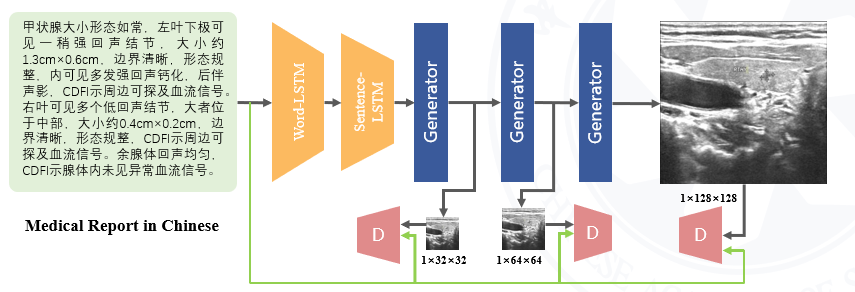

- Using GAN to generate ultrasound scan from ultrasound repots.

- Project worked at Shenzhen Institutes of Advanced Technology, Chinese Academy of Sciences.